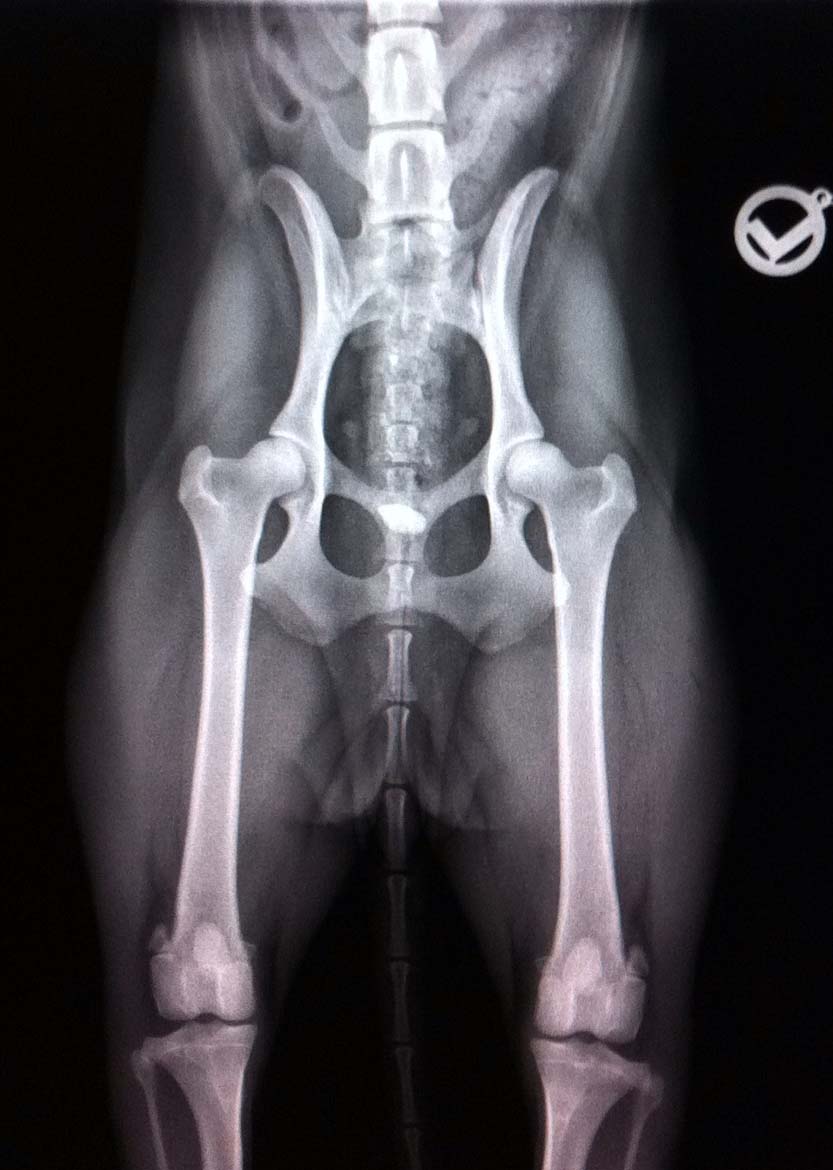

Nachdem wir erst die Augenuntersuchung gemacht hatten (Sydney ist frei von allen erblichen Augenerkrankungen) freuen wir uns nun riesig darüber, dass auch die Hüfte von unserer Sydney mit HD A2 ausgewertet wurde. Somit steht jetzt als nächster Schritt die Körung an ...... :-)